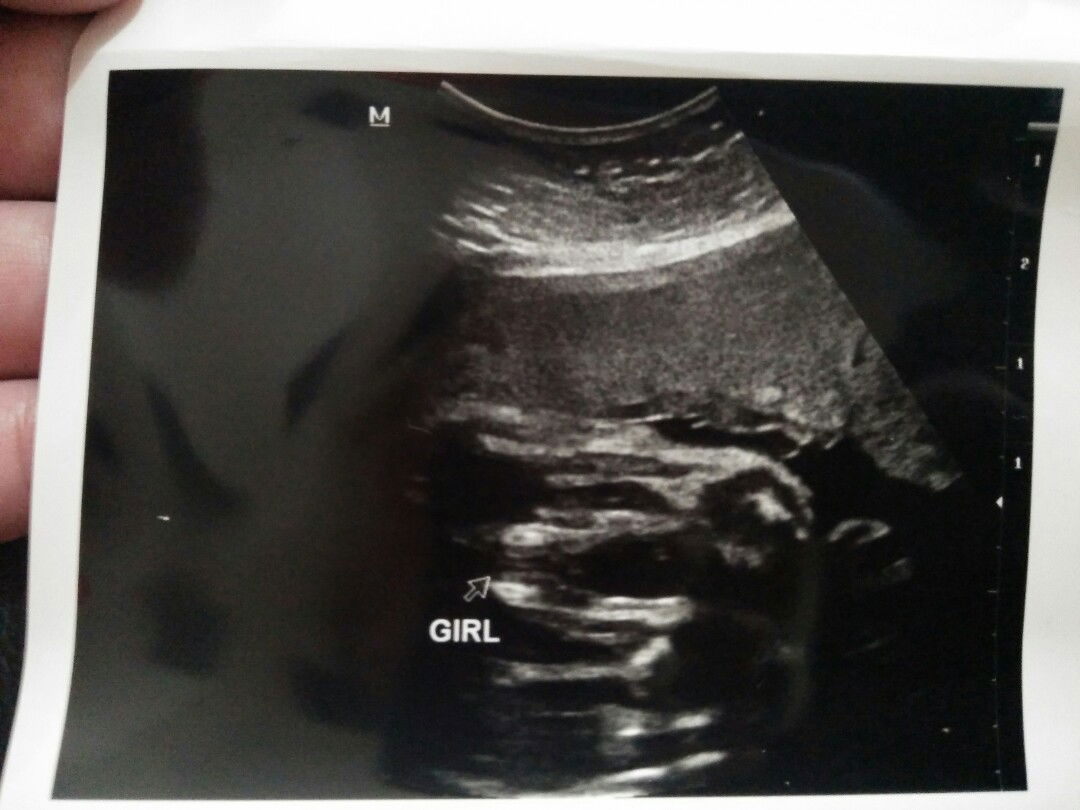

baby girl atau baby boy

Hai mommy yg ada disini..hari tu sy ada scan jantina baby di klinik swasta,doktor ckp baby girl..lepas tu sy ada appointment doktor hari ni,doktor ckp baby boy..klo mommy2 tengok hasil gambar scan yg dekat swasta tu baby apa ya?baby girl atau baby boy??